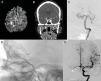

MethodsA total of six patients were treated: four patients with five aneurysms, one patient with an MCA stroke, and one patient with a meningioma requiring preoperative embolization were initially thought not to be amenable to endovascular treatment. The decision was made to treat these patients with transcirculation approaches. All patients were treated by one interventionist. One aneurysm was located in the cavernous internal carotid artery (ICA), one in the vertebral artery, two in the paraclinoid ICA, and one in a cerebellar AVM feeder vessel were treated.

ResultsFive of six patients (83%) made a full neurologic recovery. Three aneurysms were treated to complete occlusion, one aneurysm was left with small residual neck filling, and one aneurysm was not able to be treated. One patient underwent mechanical thrombectomy of a middle cerebral artery (MCA) embolus and MCA filling was restored after treatment. One patient underwent complete embolization of the deep vascular supply of a meningioma.